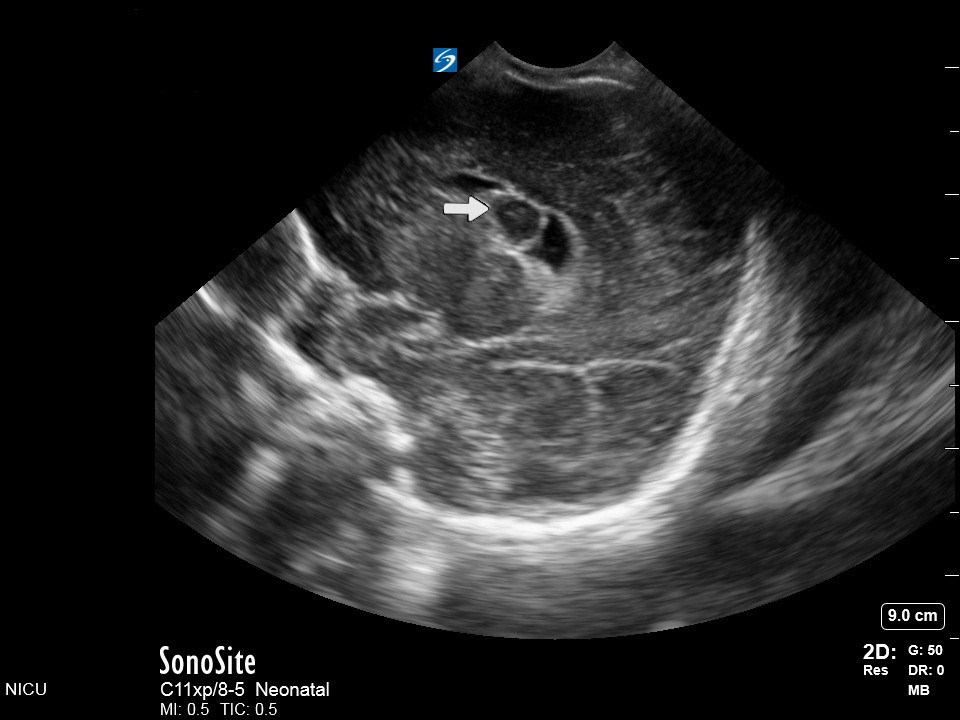

Neonatology Coronal IVH Grade 4 Image